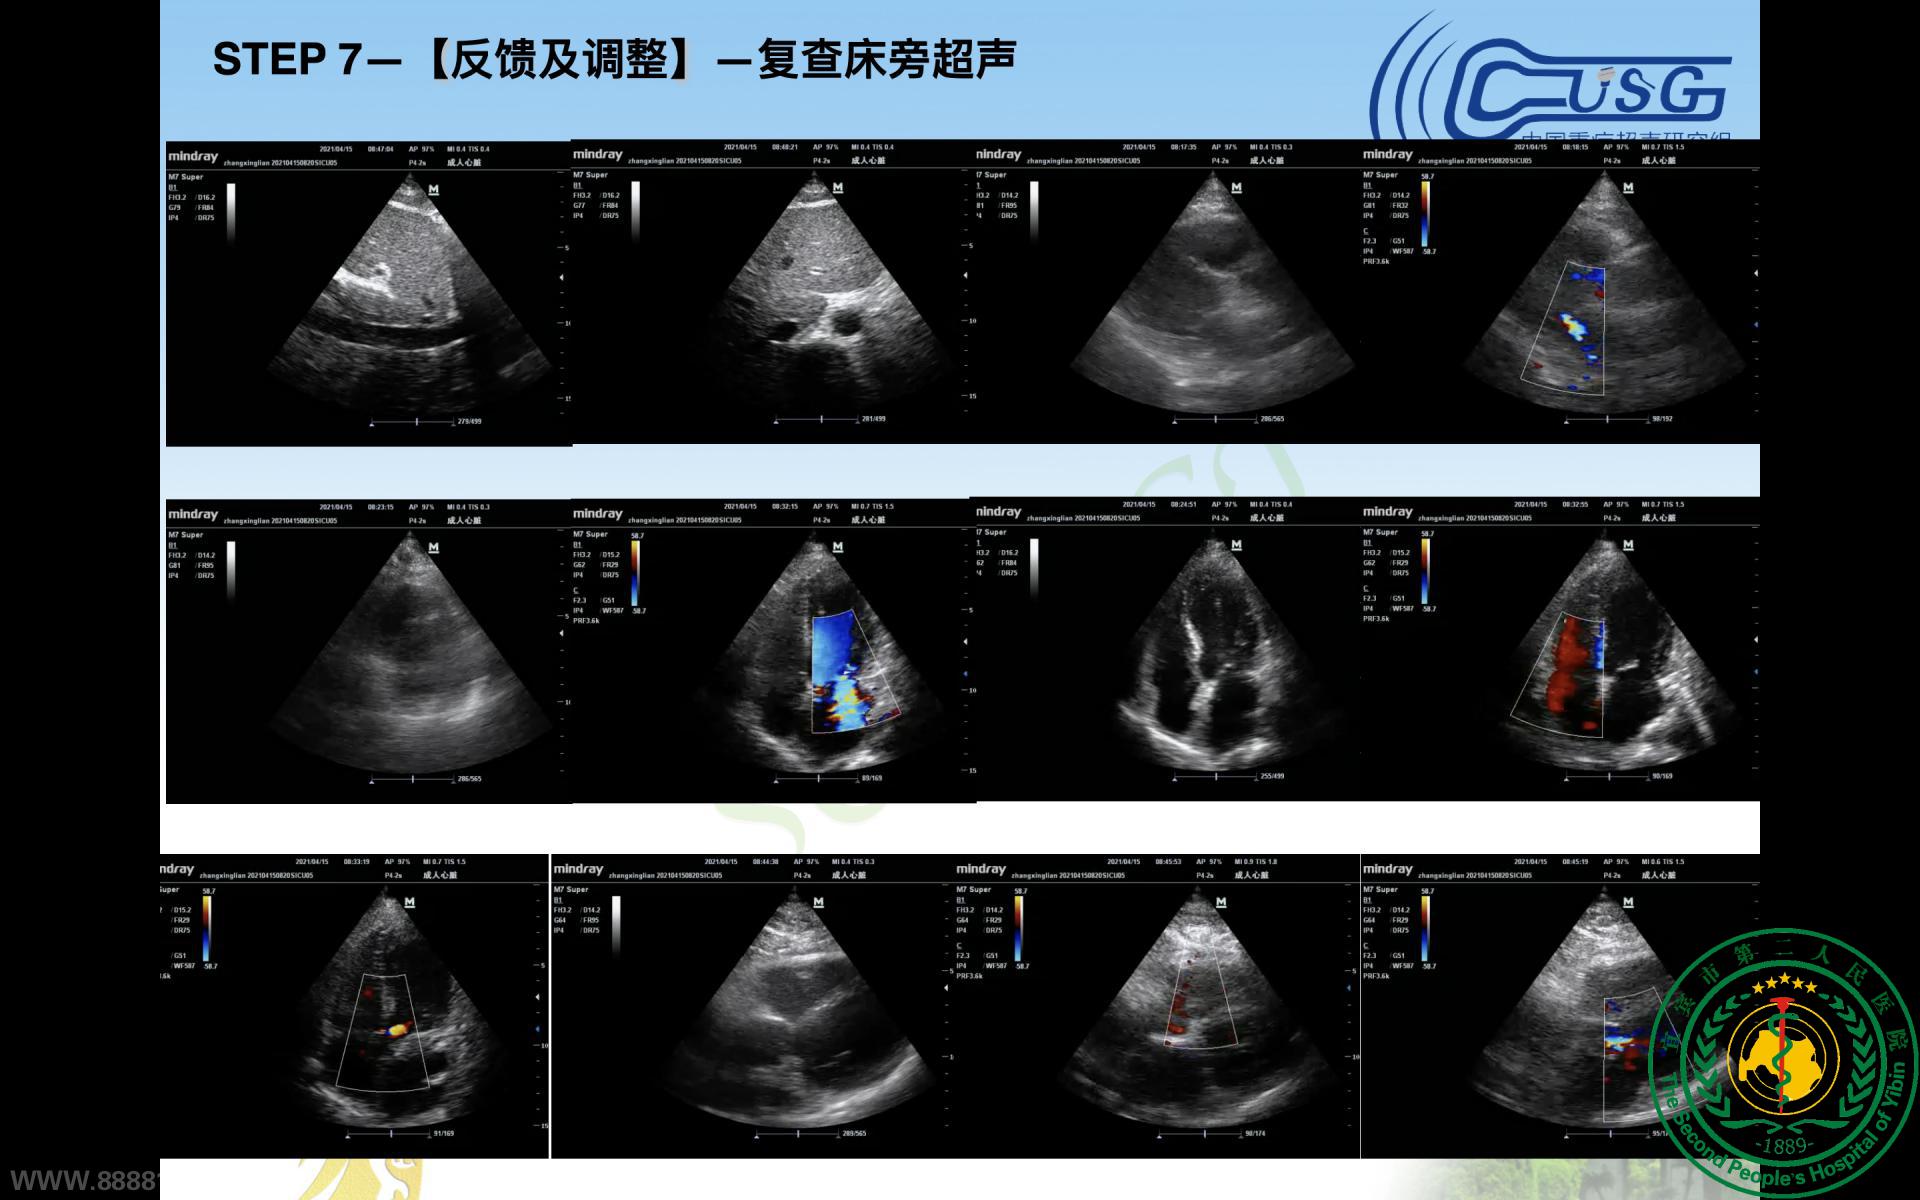

重症医学科协办四川省第十期重症超声培训会暨CCUSG重症超声巡回培训成都站基础班(宜宾分会场)圆满成功35691

宜宾市第二人民医院 图文